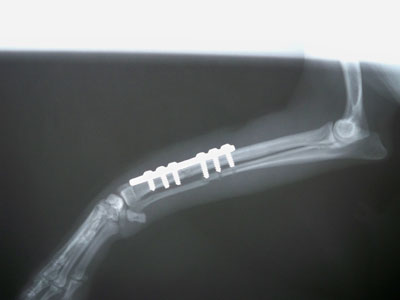

Μετά από ναρκωσή του με το αναισθησιολογικό σχήμα που ακολουθείται στα ορθοπαιδικά χειρουργεία και προσπέλαση στην έσω επιφάνεια τοποθετήθηκε μεταλλική πλάκα 2,7 mm με 8 οπές στην πρόσθια επιφάνεια της κερκίδας.Χρησιμοποιήθηκαν 6 κοχλίες 2,7mm 3 κεντρικά της καταγματικής γραμμής και 3 περιφερικά.

Μετά από 15 μέρες επέστρεψεμε την μεταλλική πλάκα σπασμένη και με το κάταγμα να παραμένει στην ίδια κατάσταση.Πραγματοποιήθηκε δεύτερο ορθοπαιδικό χειρουργείο όπου τοποθετήθηκε 3,5 mm μεταλλική πλάκα και οστεομόσχευμα.Η αγωγή που ακολουθήθηκε κατά τη διάρκεια του χειρουργείου και η μετεγχειρητική αγωγή είναι η ίδια με την προηγούμενη.Η αποκατάσταση ήταν 100 % και τα υλικά αφαιρέθηκαν 6 μήνες μετά .